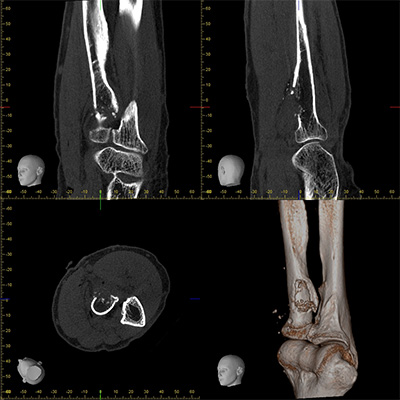

Portable iCT scanner

CT images of an upper arm and elbow